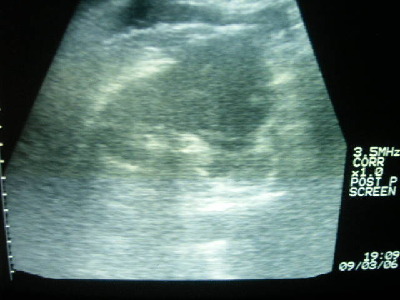

Diagnostik

Bilder